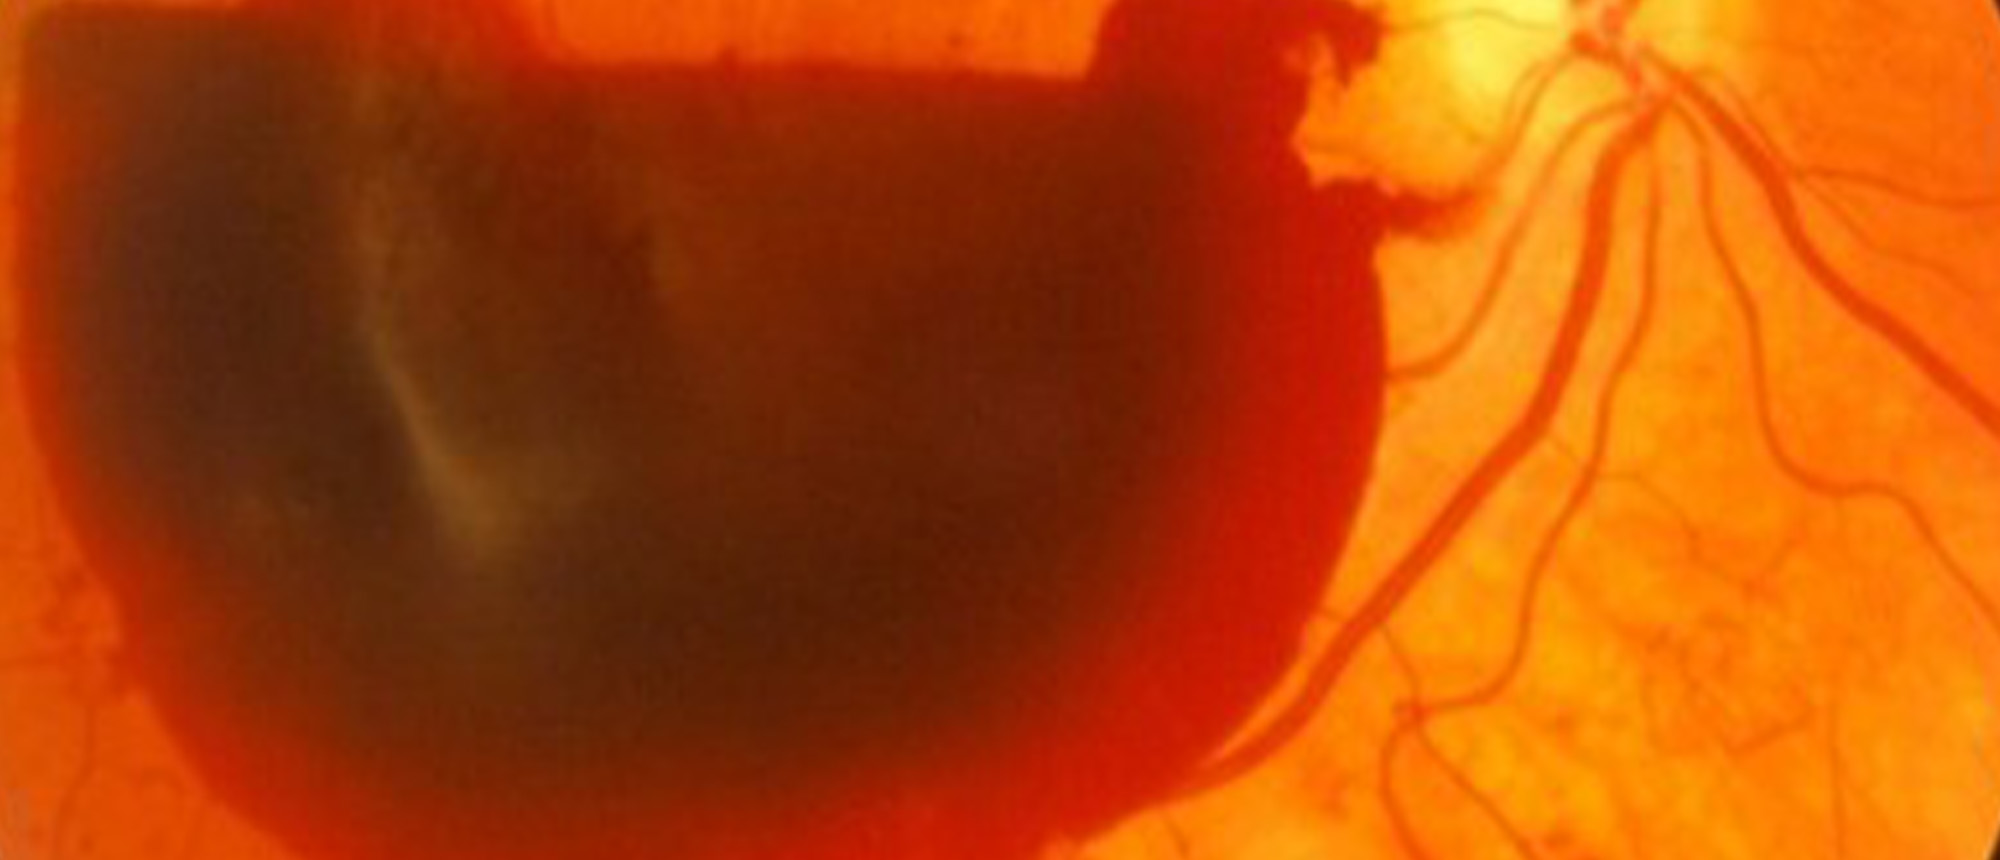

A patient with no significant past ocular history presents to the emergency department for blurred vision noticed during a recent hospital admission. The patient was recently found to have intracranial hemorrhage and anterior cerebral artery aneurysm on a CTA brain after presenting for headache. He had coiling done with neurosurgery 3 weeks prior to presentation, however, subsequent scan showed refilling of aneurysm and worsening midline shift, repeat coiling was performed. He was admitted to the neuro-ICU for monitoring. He was eventually discharged and told to present to the Bascom Palmer Emergency room for blurred vision. Examination revealed vitreous hemorrhage in both eyes overlying the macula with normal appearing peripheral retina. OCT showed sub-hyaloid hemorrhage in the right eye, while the left retina was relatively preserved. B scan ultrasonography was performed without evidence of retinal tear, only showing mobile vitreous opacities in both eyes. Overall, given the patient’s history, clinical presentation, and multimodal imaging, the diagnosis was most consistent with Terson Syndrome.